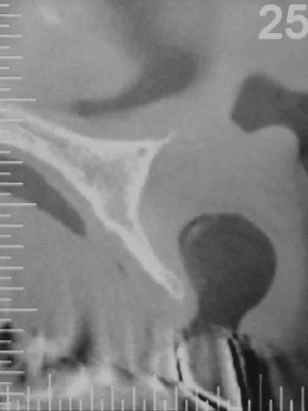

術前のCT画像。インプラントを入れられないくらい骨が痩せてしまっているためブロック骨移植によって骨の厚みを増やしてからインプラントの埋入をおこなうことになりました。

術前術後のCT画像。外側に骨のボリュームが増えているのがわかります。